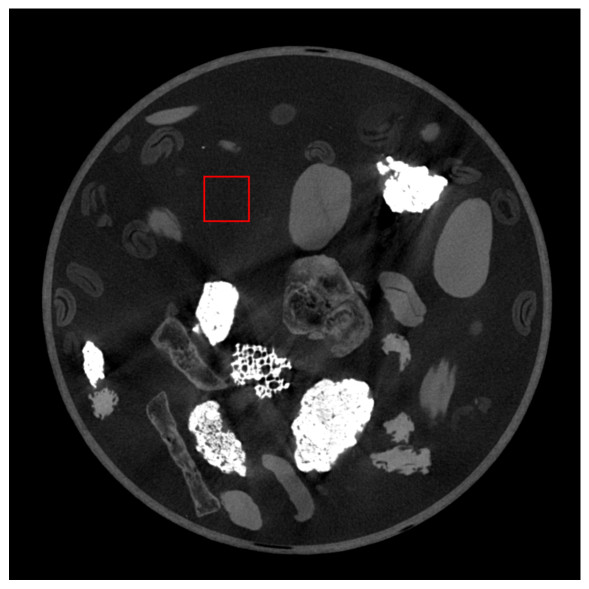

To further investigate the noise properties in these images, Figure 7 shows the distribution for an exemplary region that was assumed to be of a constant image value. Here, more deviation from the ground-truth mean value (marked as a vertical line) indicates a higher standard deviation and hence a higher noise level. As highlighted by the shadowed regions, our approach reduced the standard deviation while adhering closely to the correct mean value. While not reproducing the ground-truth image exactly, this behavior suggests that the network produces smoother imaging results than FBP and ML.

Refer to captionRefer to caption

Figure 7: Image value distribution of an exemplary constant image region for the different methods. The region of interest (ROI) is marked in red. Gaussian distribution curves are fitted to emphasize distribution differences. The black vertical line indicates the mean value of the ground-truth image in the ROI. The orange vertical line indicates our prediction’s mean value. The shadowed regions indicate the standard deviation of the GT ( ) and our method ( ).